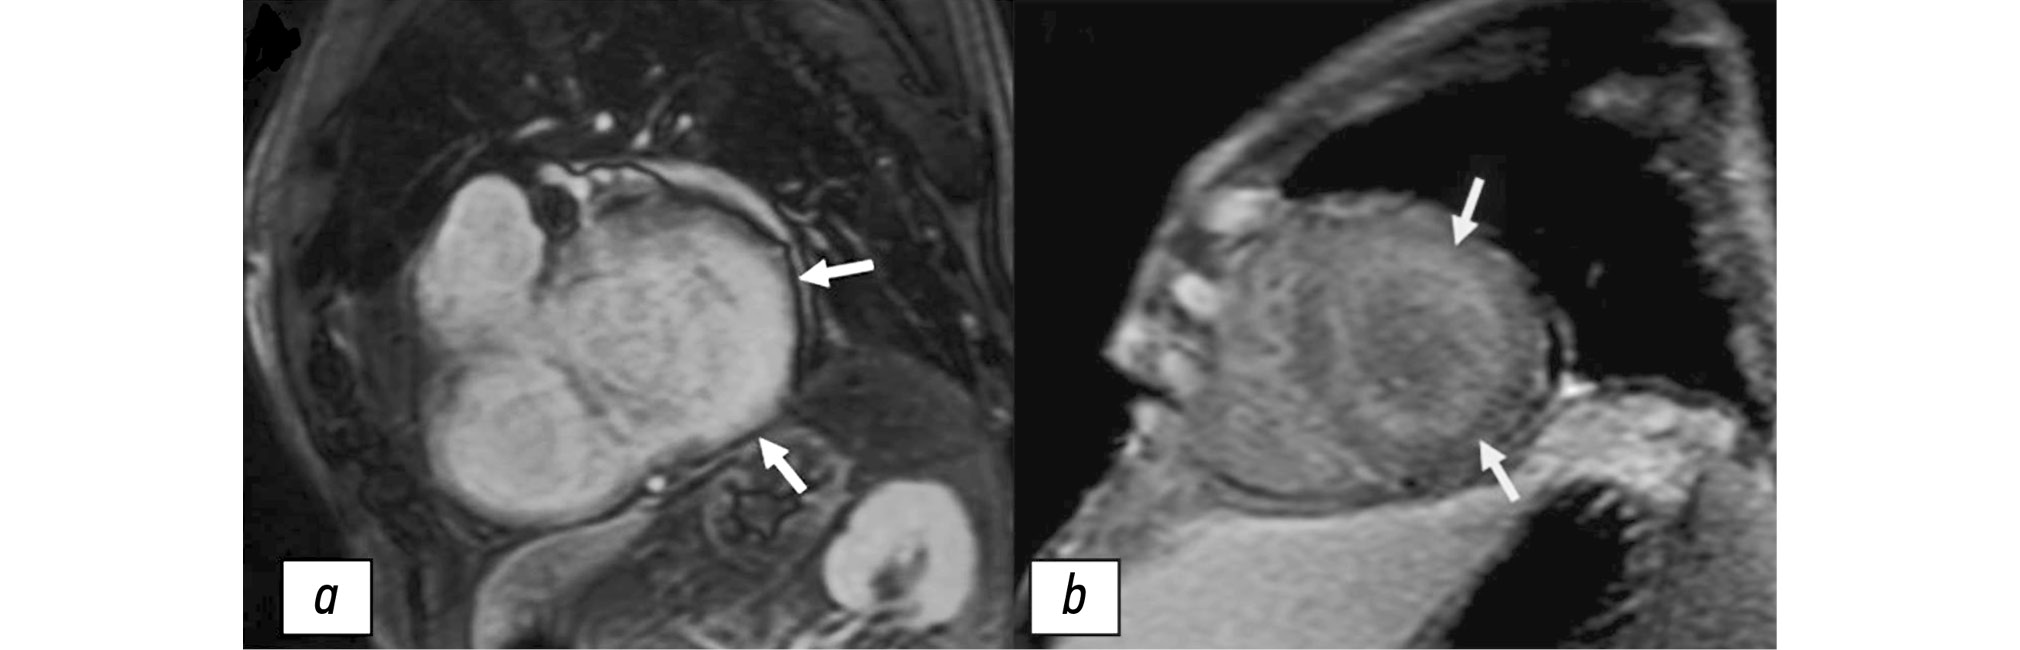

The analysis of LGE characteristics revealed specific patterns for each amyloidosis type, which can be used for the differential diagnosis. The most valuable findings are as follows:

- ATTR amyloidosis: more commonly associated with a pronounced transmural LGE at the basal and middle levels, in the inferolateral segments of the LV, with RV involvement, particularly in the interventricular septum (LV involvement) and the RV inferior wall (Fig. 8, a).

- AL amyloidosis: more commonly associated with a subendocardial LGE, mostly at the middle levels, in the antero- and inferolateral segments (Fig. 8, b).

Fig. 8. Time-delayed contrast-enhanced cardiac magnetic resonance imaging scans in transthyretin amyloidosis. a, transmural contrast uptake at the basal level (lateral segments) and intramural contrast uptake at the basal level (inferior segment) of the left ventricular myocardium (white arrows), QALE score: 15 points. b, circular subendocardial contrast uptake at the middle level (all segments) of the left ventricular myocardium (yellow arrows), QALE score: 10 points.